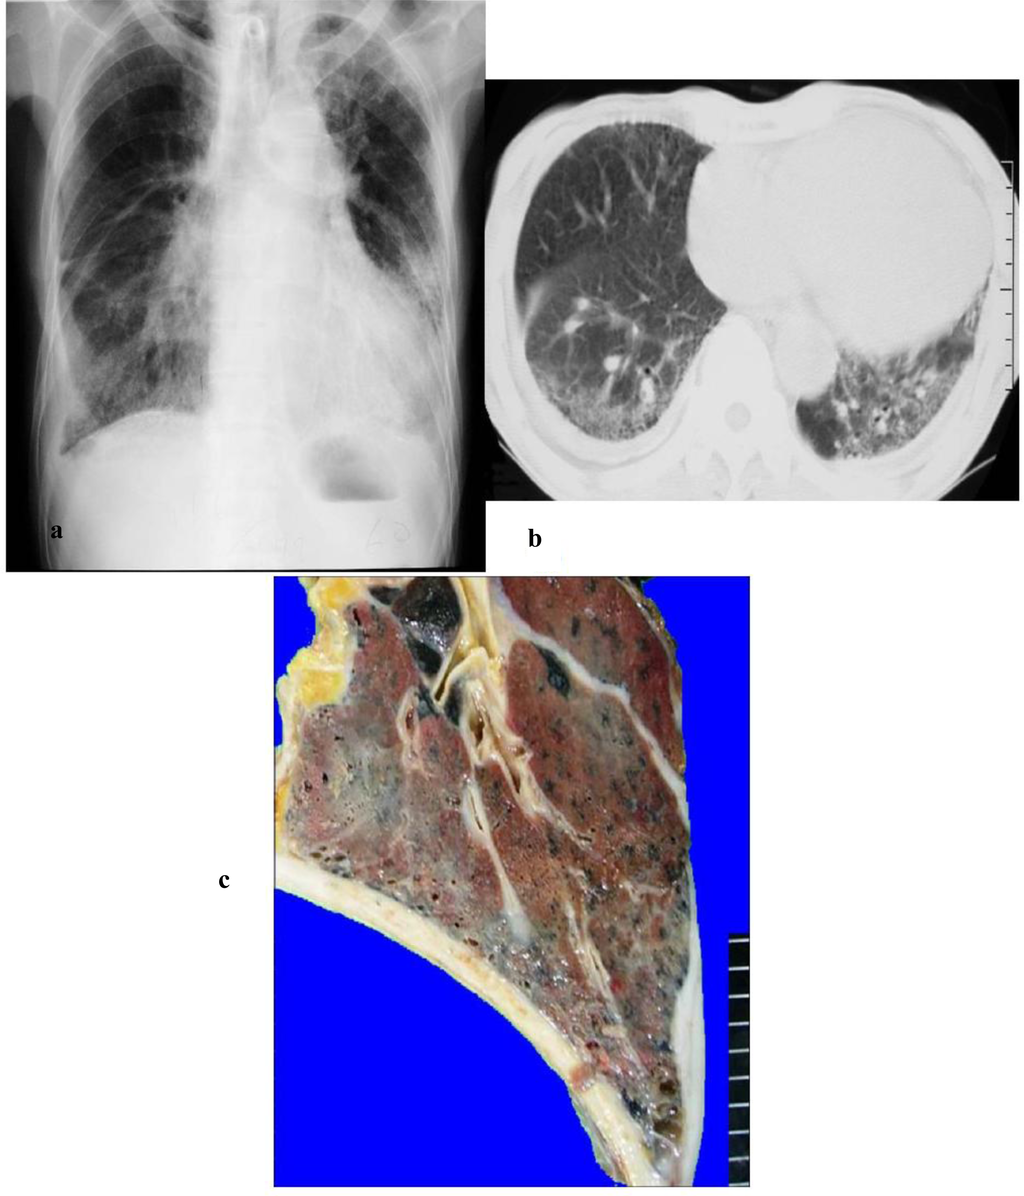

Figure 1.

This case was diagnosed as asbestosis based on chest x-ray, CT, and pathology. Radiological findings showed characteristics of ground glass shadows in both lower lungs accompanied by bilateral pleural thickening (a). Chest CT showed slight honeycombing of the lungs but mainly ground glass shadows (b). On the other hand, visual inspection of autopsied lungs indicated a few small honeycomb lungs and they were atypical (c). Histopathological findings showed fibrosis accompanied by a large number of asbestos bodies on the respiratory bronchiole wall and the surrounding area and severe fibrosis accompanied by the honeycomb lungs (d, e, f). There were more than 2,280,000 asbestos bodies/g in the lung.